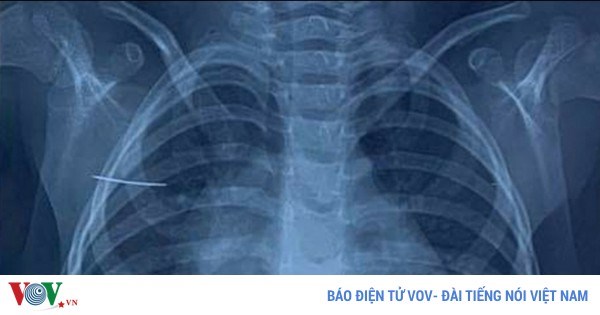

Nhập viện vì nghe “mạng xã hội” uống thuốc sốt rét chống Covid-19